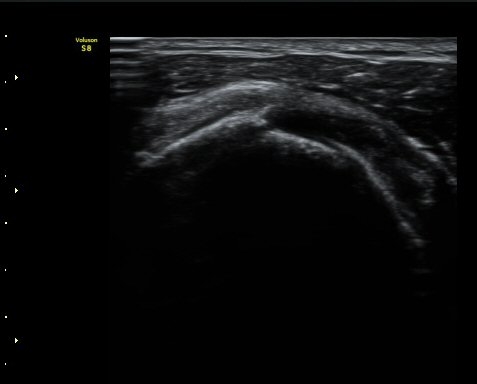

ƯÀÌ ¼Ò°ßÀ» º¸ÀÌÁö ¾ÊÀ¸³ª(±×¸² 8) ±Ø»ó°Ç ¸»´ÜºÎÀ§¿¡¼­ ´ë°áÀýÀÇ °ñ °áÇ̰ú ÇÇÁú°ñ ¿¬°á¼º

¼Ò½ÇÀ» º¸ÀδÙ(±×¸² 9, 10).